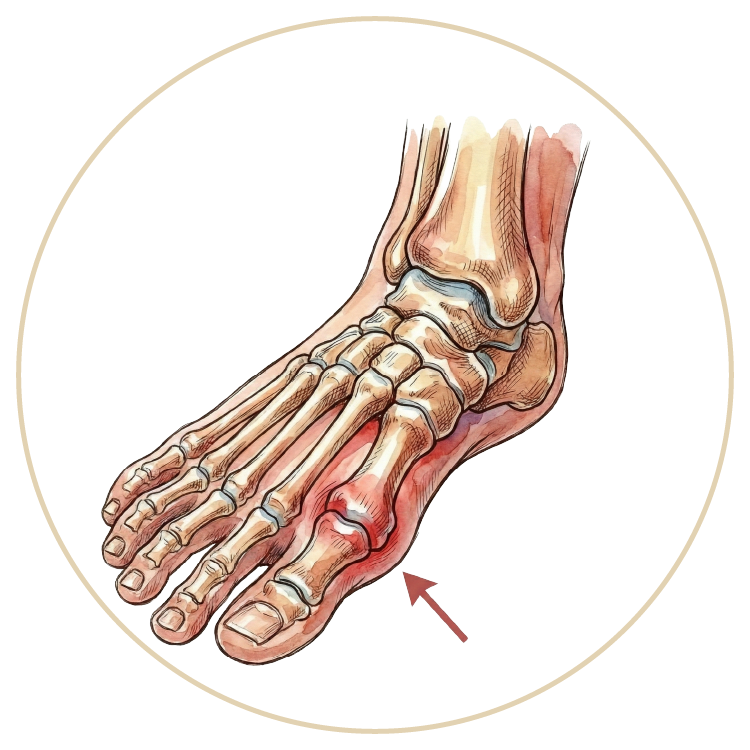

Ayak ve Ayak Bileği Hastalıkları

HalluksValgus

Halluks Rigidus